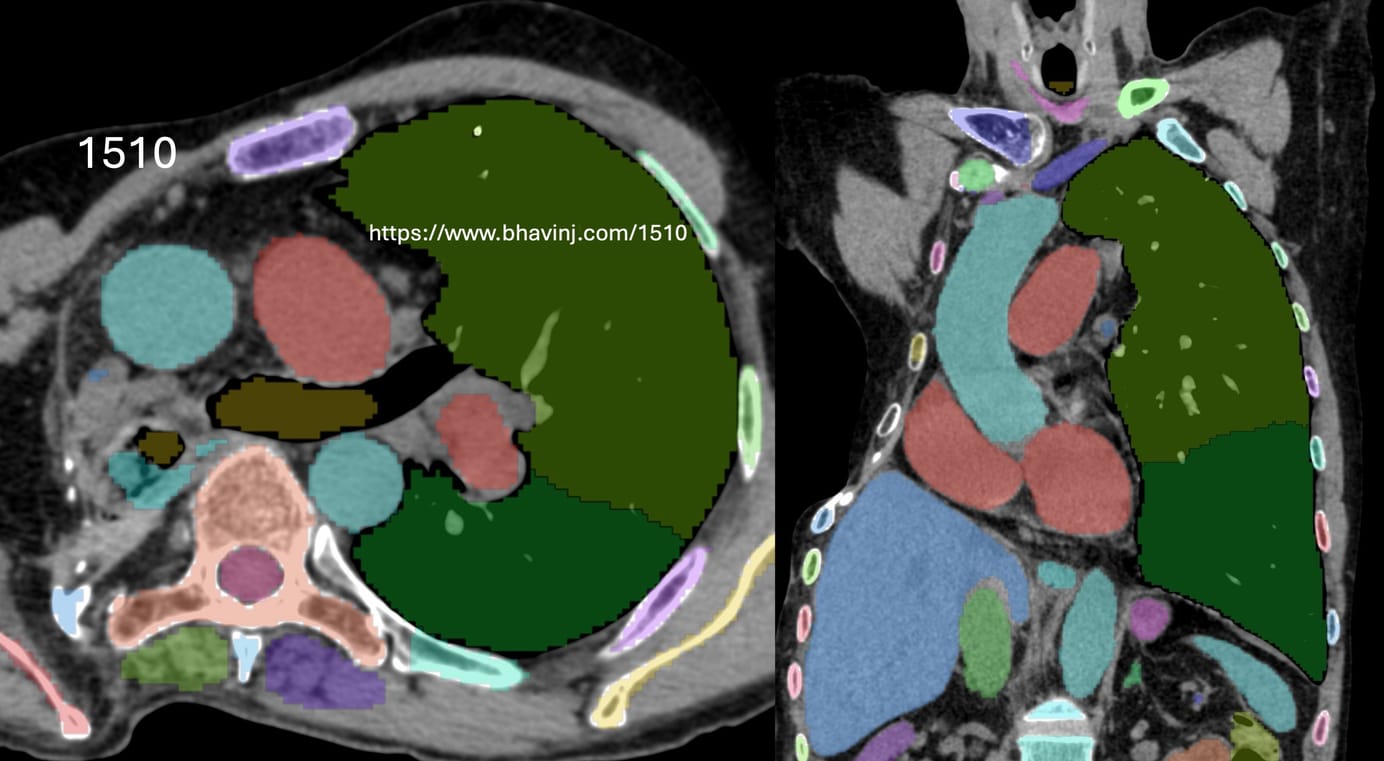

My first Geeking Out post was in Feb 2025, a year back when I wrote about setting up a workstation with two 27 inch screens using a MacMini M4 with 16GB RAM and 256GB hard disk and two 2TB externals SSDs. I have installed them wherever I read scans. I needed to make one more and this time I bought an M4 with 24GB RAM and 512 GB hard disk, so that I could use the Totalsegmentator plugin in OsirixMD, which needs 24GB RAM to run. The CT scan segmentation is just brilliant as this one image shows and it was worth the upgrade of one of my workstations just to be able to do this. Each organ is color coded and labeled (this is a patient of thoracoplasty that I did a Case of the Day of last week)